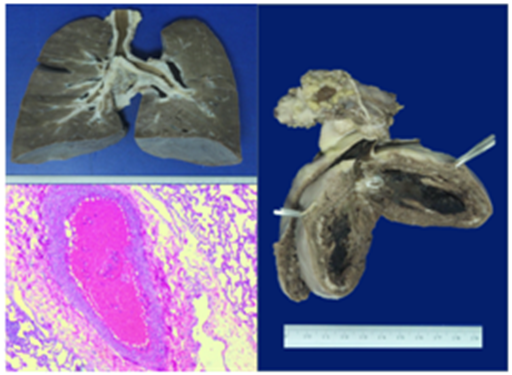

Considering the previous signs and laboratory parameters; treatment was started with antibiotic ceftriaxone 50 mg/kg and requirement fluid therapy; she evolved with cardiopulmonary deterioration; with persistent desaturation with 100% inspired oxygen, increased respiratory effort and sinusal tachycardia; we performed endotracheal intubation followed by clinical deterioration with hypotension, bradycardia and cardiac arrest; we started advance CPR, during the maneuvers she developed ventricular arrhythmias, fibrillation with no response to treatment and no return to spontaneous circulation, declaring time of death 10:00 in the morning. An autopsy was performed and reported the presence of a pulmonary thrombosis and an atrioventricular intracavitary thrombi (Figure 2 & 3).

Figure 2 & 3 Pulmonary thrombosis and atrioventricular intracavitary thrombi.